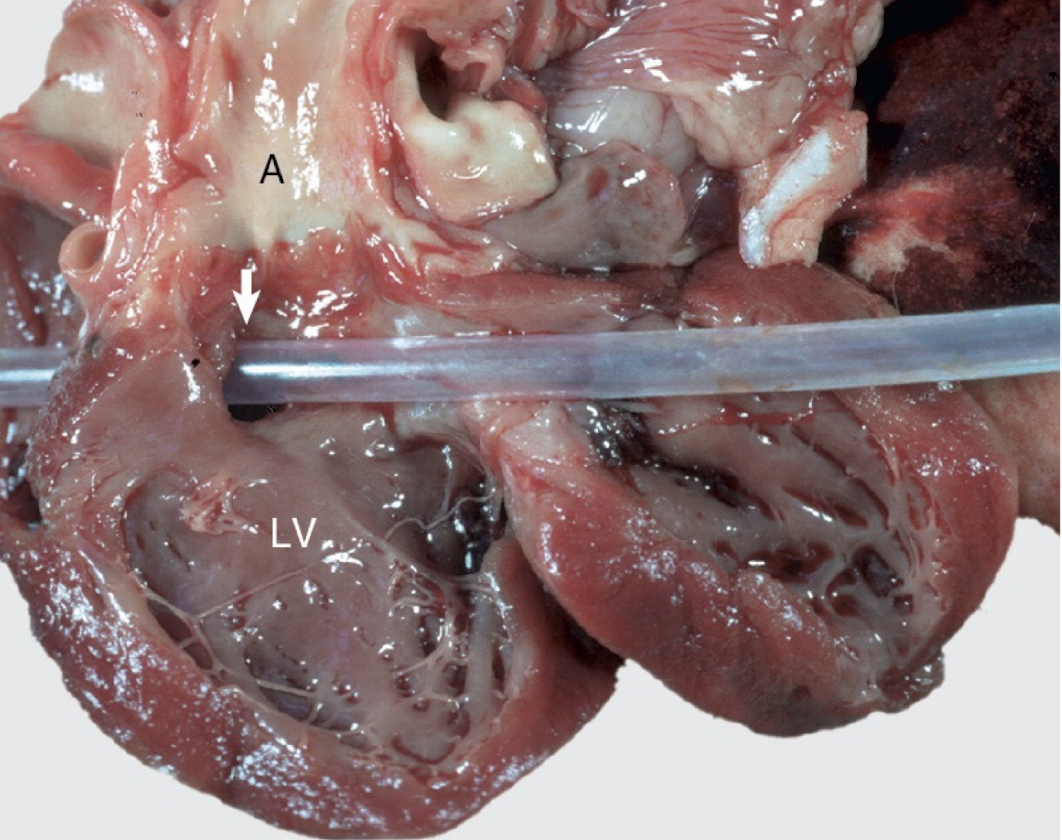

14

Q

Name/cause of this lesion

A

Jet lesions of SAS (caused by turbulent flow hitting the aortic wall)